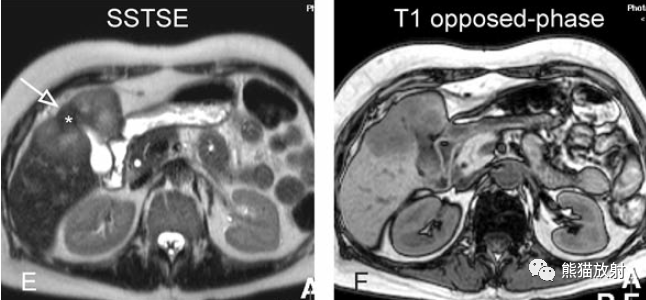

另一例膽囊癌,T2WI及增強(qiáng)延遲期顯示膽囊壁不均勻增厚并明顯強(qiáng)化。